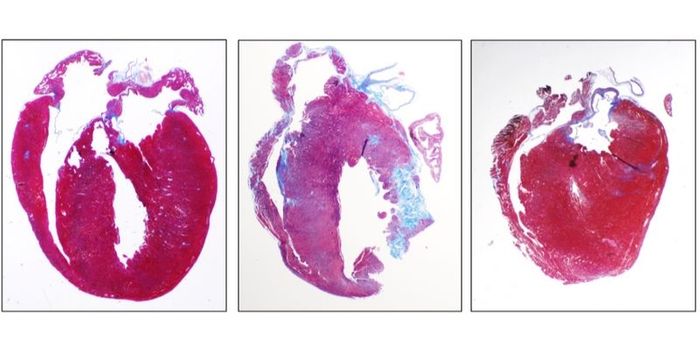

JAN 26, 2021Genetics & GenomicsScientists have found a way to explain why a heart condition called hypertrophic cardiomyopathy (HCM) can be so differen ...